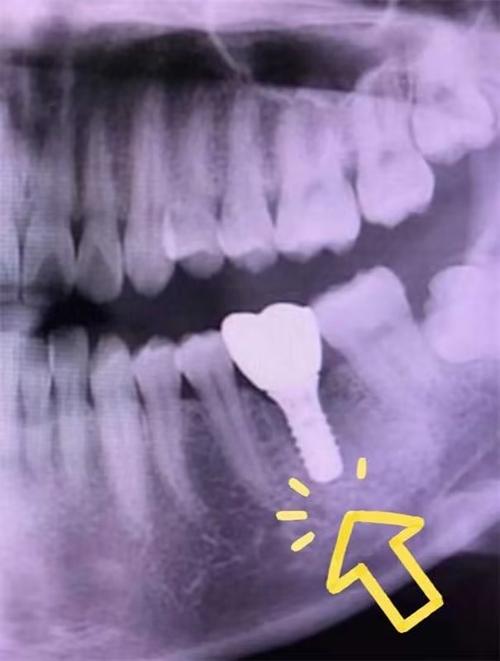

- 临床实践: 在80年代末至90年代初,九院就已经开始为符合条件的患者实施种植牙手术,并积累了宝贵的早期临床经验,这被认为是上海地区最早、最系统、最持续开展种植牙临床实践的机构。

- 第一例手术: 具体是哪一年哪一家医院完成了上海地区第一例种植牙手术,目前难以考证,很可能是在1988-1992年这个区间内,由九院或其他顶尖医院的专家团队完成。